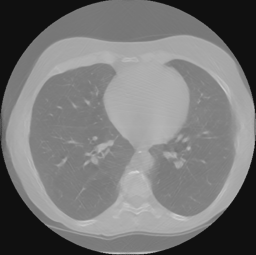

Refer to caption

Figure 9: The inpainted sinogram and reconstructed images for test datasets of lung CT from Data Science Bowl 2017. We compair three reconstrucion methods: FBP, our proposed supervised-trained network, and iterative SART reconstrucion with TV regularization. Both the proposed network and SART-TV method reduce the streaking artifacts. And our results have less cartoon-like artifacts than SART-TV. The display window is [-1, 1].

Fig 9 and Table I demonstrate the experiment results for the lung CT data. Both the proposed network and SART-TV method reduce the streaking artifacts caused by the sinogram inconsistencies in angle, while SART-TV introduced piecewise constant cartoon-like artifacts because of the TV normalization. The quantitative studies indicate the superiority of the proposed method in terms of absolute error and structural.

TABLE I: Quantitative Comparsion for FBP, SART-TV and Proposed Method for Lung CT test dataset (113 images)

FBP SART-TV Proposed

avg. PSNR(dB) 22.51 25.23 33.86

avg. SSIM 0.9249 0.9088 0.9781